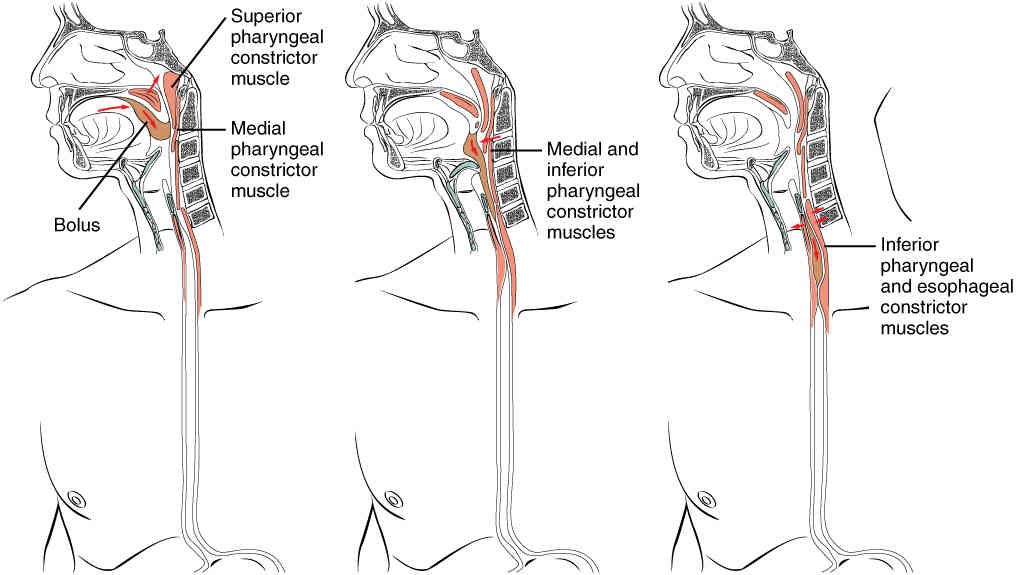

This page is under construction. For now, it is just a resource of the images found in the OpenStax Anatomy and Physiology Handbook. It wil slowly change into a revision tool. Each slide has a number. Use this to refer to the slide. When completed, it will have an unlabelled section, with labelled slides in parallel. On the unlabelled slides, write your answer and use the labelled slide to assess yourself. Keep track by also noting the number on each slide. Improvement at each attempt is important, more so than full marks on a first attempt.